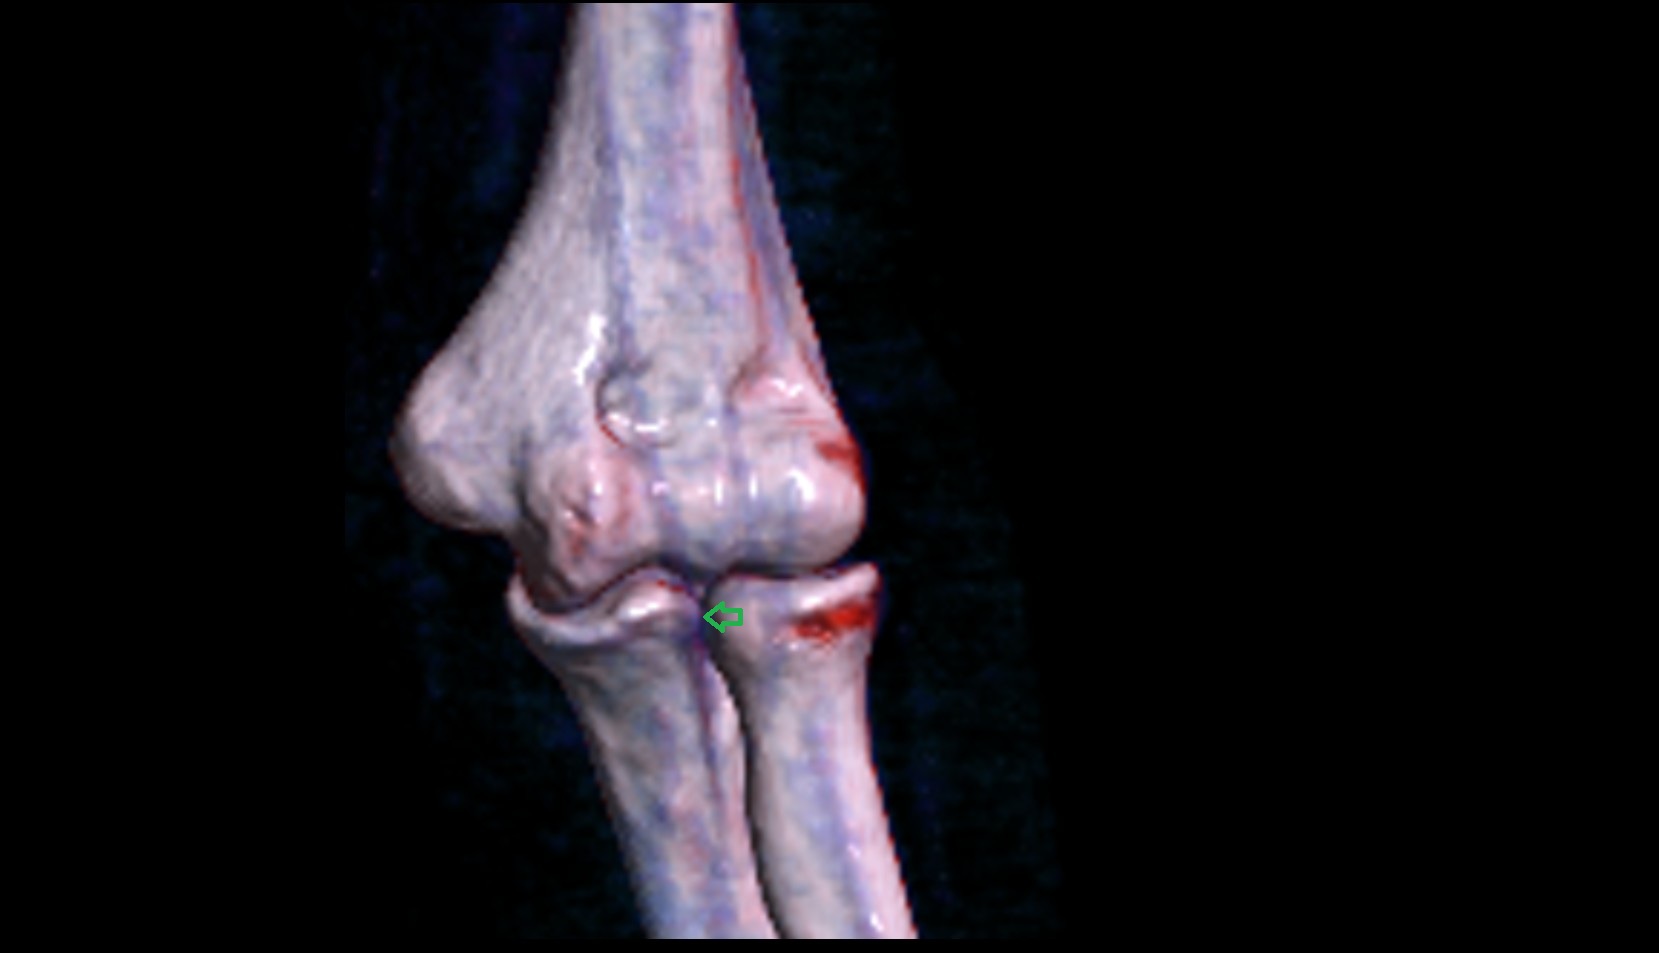

- Knee Joint

- Elbow joint